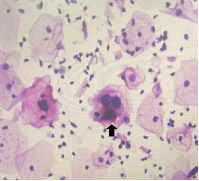

箭头所指的细胞虽然也发生了核的改变,但没有那么严重,不能排除宫颈细胞没有发生病变,需定期复查。

箭头所指细胞核的周围出现了空晕,我们称其为“挖空化”,提示宫颈细胞发生了可疑鳞状细胞低度病变。